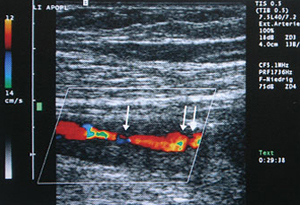

Ultraschallbild (Duplexsonographie):

verengte Schlagader